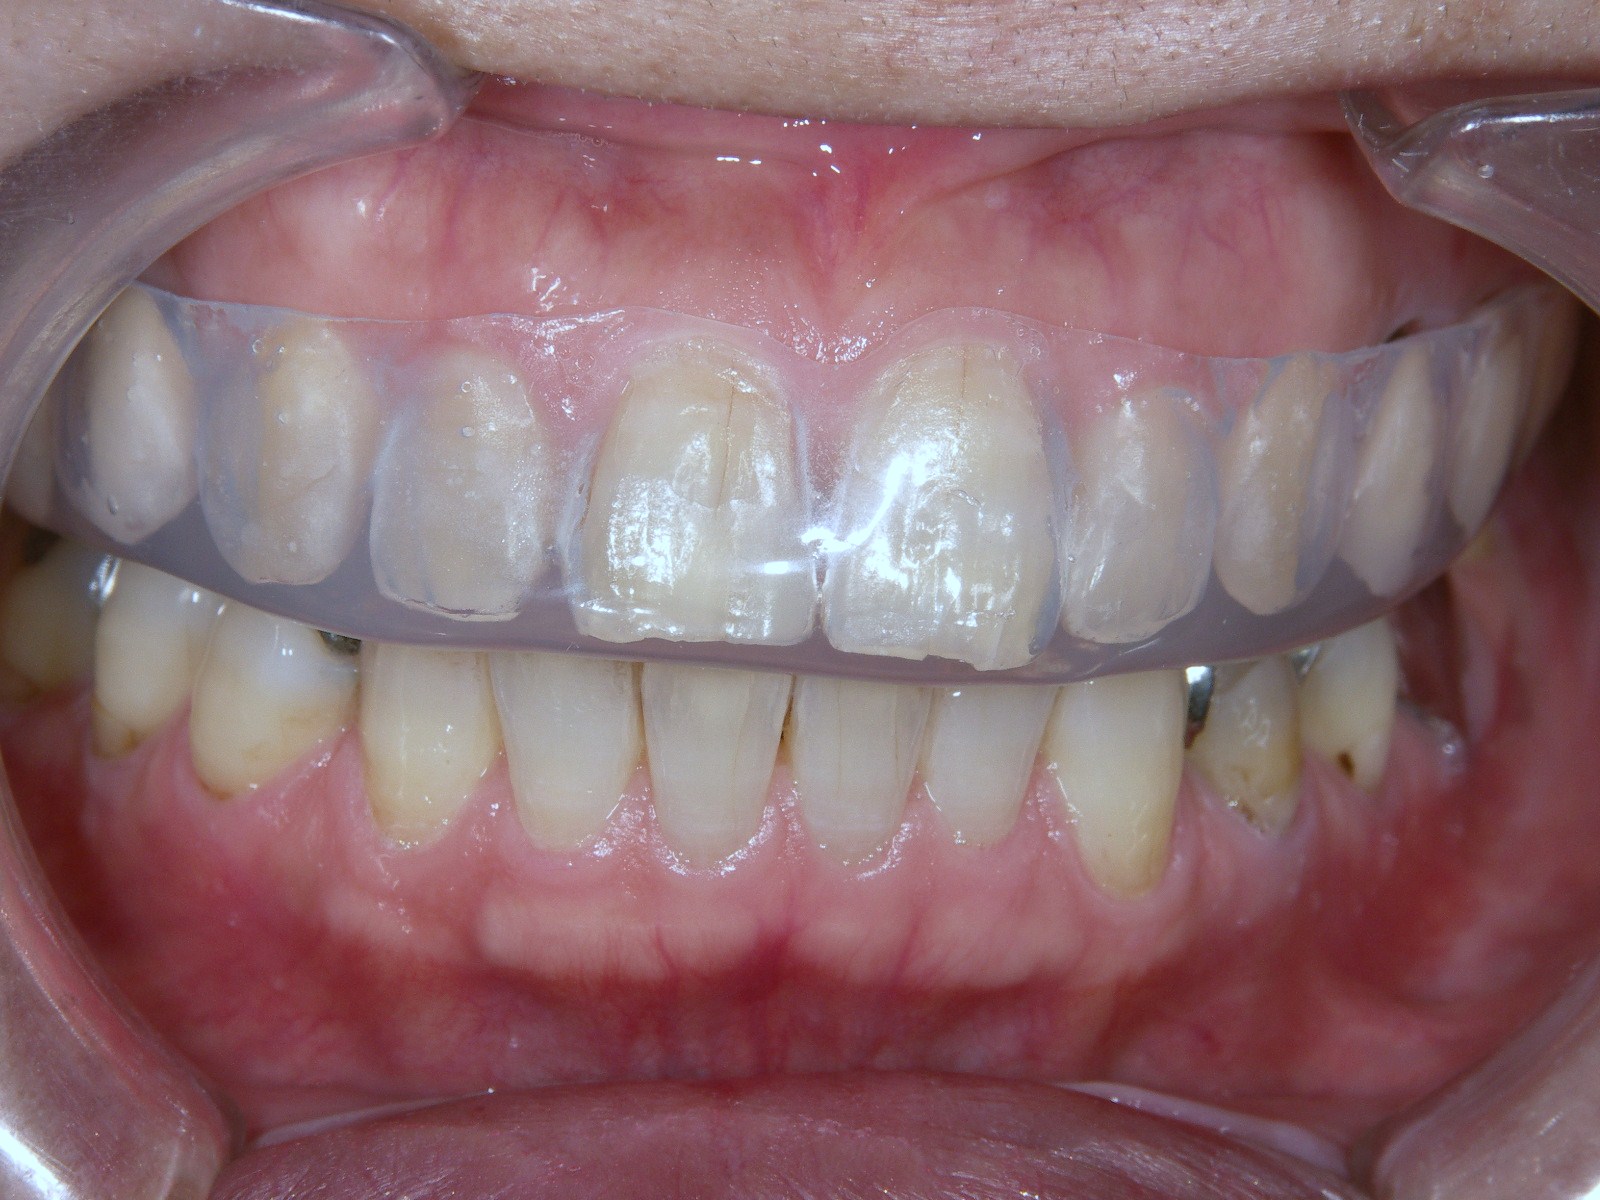

①食いしばりや歯ぎしりなどが原因で知覚過敏症になっていると思われる場合はナイトガードという歯をカバーする器具を使用し、歯ぎしりによるエナメル質・歯周組織の破壊を防ぐ治療を行います。

歯ぎしりやくいしばりをしていませんか?

歯ぎしりやくいしばりをしている方は、歯質の摩耗・微小破折や歯周病の悪化をきたしやすいのですが、かなり折れた歯質や骨は結局戻ることはできません。

もしそうなれば噛み癖のある方は、症状が現れる前にナイトガードを装着して予防することを推奨いたします。